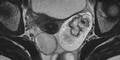

Am Eierstock der Frau hatte sich eine Zyste gebildet - ein mit Flüssigkeit gefüllter Hohlraum - die zu einem Geschwülst von etwa einem Meter Durchmesser angewachsen war. „Ich habe noch nie eine so große Zyste gesehen“, schrieb der Leiter der gynäkologischen Abteilung, Tomasz Kluz, in einer Erklärung.

Die Untersuchungen seien sehr schwierig gewesen, da die Patientin wegen ihres enormen Bauchumfangs nicht in den Computertomografen gepasst habe. Bei der Operation ließen die Ärzte zuerst rund 100 Liter Flüssigkeit ab und entfernten danach die Zyste.